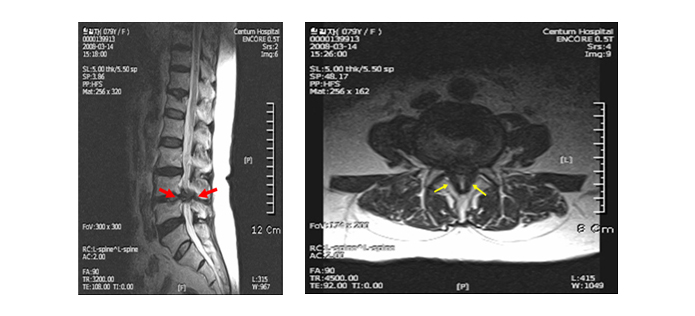

협착증 환자는 척추관을 둘러싼 그 부근 전체, 뼈, 인대, 후관절, 디스크 등이 깡그리 으로 퇴보되어 두꺼워지므로 다리로 가는 신경이 눌려서 근력이 약화되고 근육이 위축됩니다.

퇴행으로 기인해서 뼈도 골극이 자라 두꺼워지고, 후관절도 두꺼워지고, 척추관 안에 있는 인대도 두꺼워지고, 앞에 있는 디스크도 수분이 빠져 납작해지면서 척추관 공간 안을 좁게 만들고요. 이렇듯 척추관을 둘러싼 근처 전체가 다 두꺼워지고 해서 척추관이 좁아질 수밖에 없는데요.

그리고 척추관이 좁아지니까 그 가운데의 신경이 압박되어 신경성 파행, 즉 걸음을 걸으면 다리가 아픈 증상이 나타나게 됩니다.